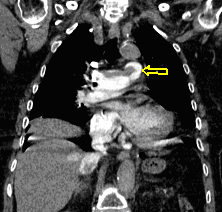

22. Central lung tumor with mediastinal lymphadenopathy. CT coronal and sagittal reconstructions.

70 year old man, COPD, hoarse. Right hilar mass, bronchoscopy was negative.

The larynx is rotated to the right, no motion of the right side of the larynx can be observed, swollen left plica ventricularis area.

CT: 13x11 mm large nodular mass in the left 10th segment. Bilateral hilar lymphadenomegaly with central hypodensity. A 34x21 mm large lymph node conglomeration can be observed in subcarinal location (peripheral contrast enhancement). Lymphadenopathy in the aortopulmonary window (15 mm large), and a 26 mm large lymph node can be observed in paraaortic location above the trachea bifurcation which has an esophagus-compressing effect. In the superior chest aperture there is a 38x28 large fused lymph node conglomerate which causes the left shift of the esophagus and trachea.